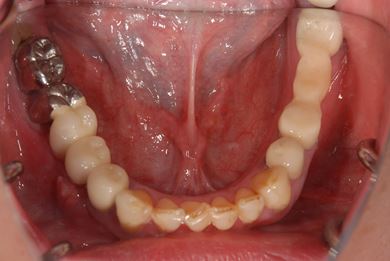

インプラントの症例写真 IMPLANT

骨再生インプラント治療

| カテゴリー | 【インプラント治療】【セラミック治療】 | ||||||||||||||||||||||||||||||||

| 性別/年齢 | 女性 / 40歳 | ||||||||||||||||||||||||||||||||

| 主訴 | 右下のブリッジが外れているかもしれないという診断を受けましたが、開けてみないとわからない、場合によっては部分入れ歯と言われ、セカンドオピニオンを希望。腫れがあるのも気になります。 | ||||||||||||||||||||||||||||||||

| 治療方針 | 右下奥、骨再生法によりインプラント治療を可能にする。 | ||||||||||||||||||||||||||||||||

| 治療内容 | インプラント3本(GBR、テンポラリーインプラント+仮歯)、ハイブリッドセラミックブリッジ3本、ハイブリッドセラミッククラウン2本 | ||||||||||||||||||||||||||||||||

| 総治療費 | 1,524,338円 | ||||||||||||||||||||||||||||||||

| 治療期間 | 1年0ヶ月 |